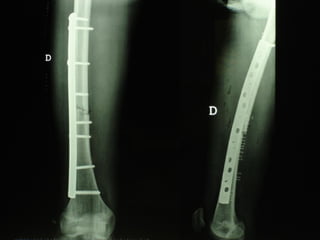

Dal Gennaio 2000 al Febbraio 2006 abbiamo trattato 167 fratture chiuse  con placca percutanea  in 164 pazienti :  27 lesioni diafisarie di gamba, 12 piloni tibiali ,  11 fratture prossimali di tibia, 36 fratture sovracondiloidee di femore, 17 fratture diafisarie di femore, 43 fratture metaepifisarie prossimali di omero, 21 diafisarie d’omero.  156 guarigioni 8 fallimenti

I buoni risultati ottenuti dipendono da 5 punti fondamentali:   una accurata riduzione percutanea della frattura  precise vie di accesso  l’utilizzo della placca che consenta il più lungo braccio di leva possibile il pretensionamento della placca  una sintesi con un ridotto numero di viti

Placche lunghe e pretensionate

Placche lunghe e pretensionate Sintesi con un ridotto numero di viti

VANTAGGI CHIRURGIA MININVASIVA Mini Open Inserimento della placca sottocutaneo per scivolamento Viti percutanee Preservazione dei tessuti molli Ridotto danno vascolare Rapida ripresa funzionale

Conclusioni Riduzione  anatomica Minimo trauma chirurgico Corretto equilibrio fra elasticità e stabilità Precoce mobilizzazione